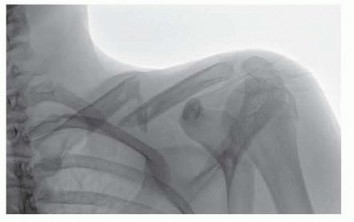

Mastering O.R.I.F. for Displaced Proximal Humeral Fractures

DEFINITION Proximal humerus fractures may involve the surgical neck, the greater tuberosity, and/or the lesse…